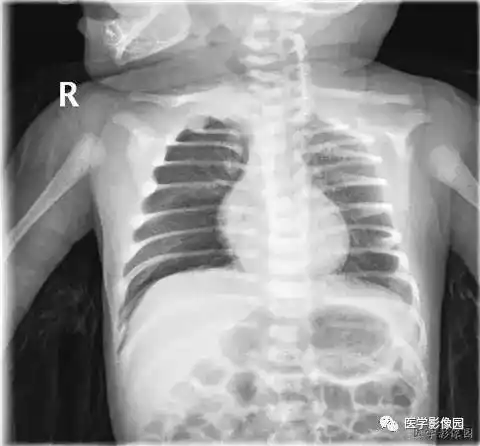

女童未及时就医诊断小儿支气管肺炎联合用药得以缓解

小孩四岁发烧不退诊断为肺炎,帮忙看下两次片子是否好了

宝宝一岁支气管肺炎

孩子3周岁多点,支气管肺炎入院治疗,6天后,孩子明显好转,医生依然让

一岁 肺炎